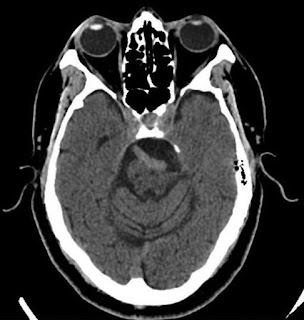

A 60‑year‑old male presented with progressively severe left

facial pain with 8 years of onset. The pain was stabbing on quality and

occurred in paroxysmal attacks in V2 and V3 trigeminal territories with

duration of approximately 30 s–1 min. He was previously healthy and his family

history was unremarkable. The neurological examination showed facial trigger

points in the left maxillary region. Furthermore, he said that brushing teeth

and shaving triggered pain. Laboratory tests were within the normal limits. A

noncontrast head computed tomography was requested.